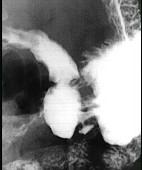

问题 男,24岁,中上腹痛,柏油样便,面色苍白,钡餐检查如图,可能的诊断为 ( )

选项 A.胃癌 B.胃溃疡伴良性狭窄 C.平滑肌肉瘤 D.胃间质瘤 E.胃淋巴瘤

答案 B